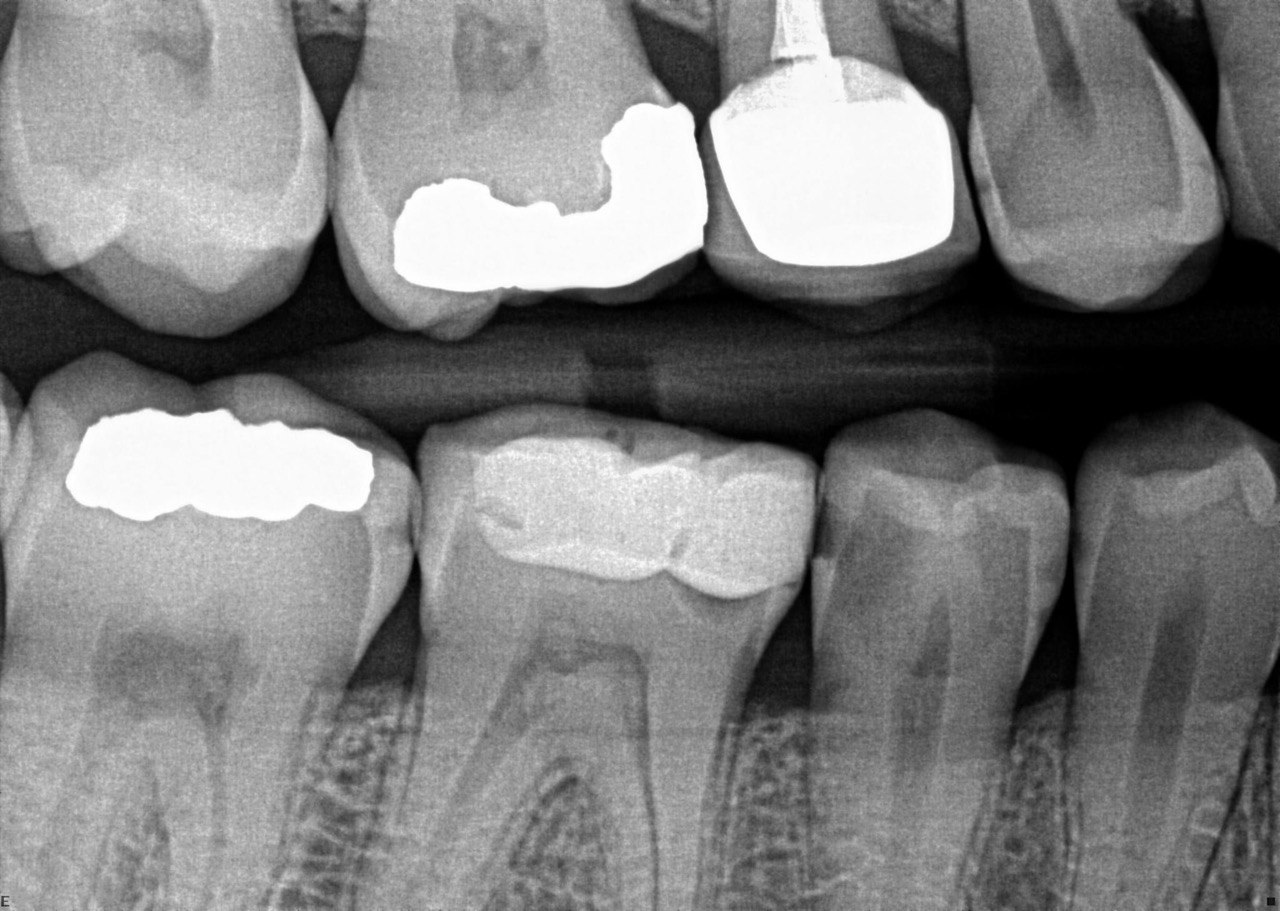

Quistion 11: What are the conditions of the distal and mesial surfaces of the tooth # 4.5 respectively?

Question 12: What option can describe the mesial surface of the tooth # 3.7?

Question 13: What option can describe the mesial surface of the tooth # 3.8?

Question 14: What option can describe the mesial surface of the tooth # 3.4?

Question 15: What option can be selected for treatment of the caries in mesial surface of the tooth # 3.4?

Question 16: What option can be chosen for the treatment of the mesial surface of the tooth # 3.7?

Question 17: What are the caries extention in distal of the tooth # 2.4 and mesial surface of the tooth # 2.5 respectively?

Question 18: What is the option that can describe the distal surface of the tooth # 1.7?

Question 19: What is the option that can describe the mesial surface of the tooth # 1.8?

Question 20: What is the option that can describe the distal surface of the tooth # 4.5?

Question 21: What options can describe the mesial and distal surfaces of the tooth # 4.7 respectively?

Question 22: What codition cannot be seen in the lower teeth in this X ray?

Question 23: What option can describe the distal surface of the tooth # 4.5?

Question 24: Which condition can be detected in the following X ray?

Question 25: What treatment is appropriate for distal surface of the tooth # 3.4 and mesial surface of the tooth # 3.5?